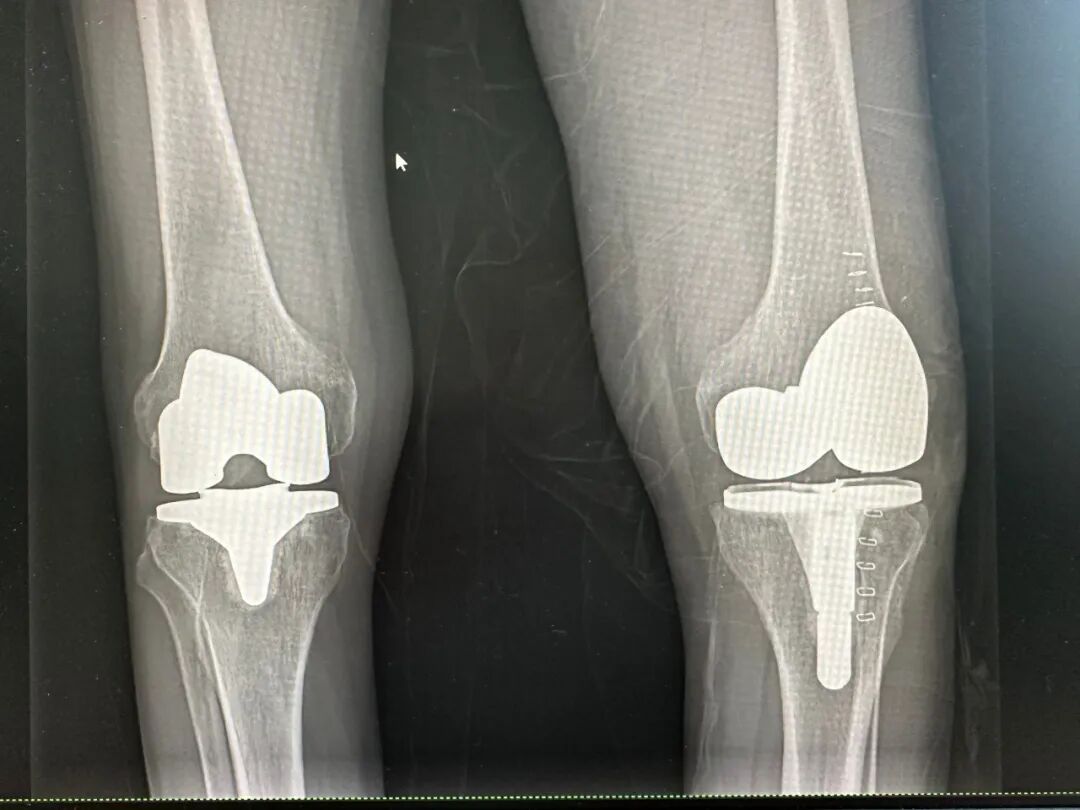

在完善术前准备后,骨科团队顺利为患者实施左全膝关节置换术。术中可见关节软骨磨损严重,关节间隙明显狭窄,骨质增生显著,医生通过精准切骨、力线重建及软组织平衡调整,顺利完成假体植入。手术进展顺利,出血量少,关节稳定性与活动度均达到预期效果。